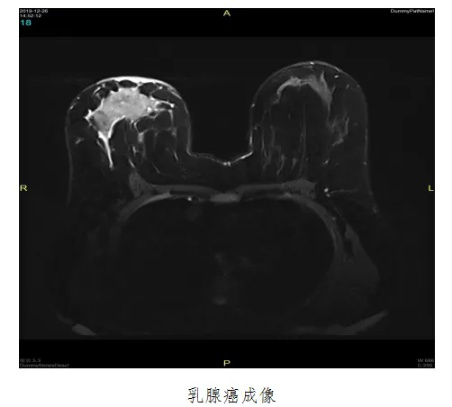

乳腺癌是我国近几年来发病率增速最快的癌症之一,严重危害女性的身心健康。如果能够早期发现并及时治疗,患者5年生存率可达70%。而磁共振乳腺成像的优势恰恰在于早发现,其对于乳腺癌早期诊断具有重要临床价值。我院超导1.5T磁共振已引进乳腺线圈,乳腺磁共振扫描现已为常规检查及体检项目,填补了安达医疗的空白。

1. 乳腺增生性病变、囊肿、腺瘤、乳腺癌等;

2. 评价钼靶或超声检查发现的可疑病变;

3. 乳腺癌的分期及评估新辅助化疗疗效;

4. 判断乳腺癌术后有无复发;

5. 高发人群乳腺癌的筛查,如乳腺癌家族史;